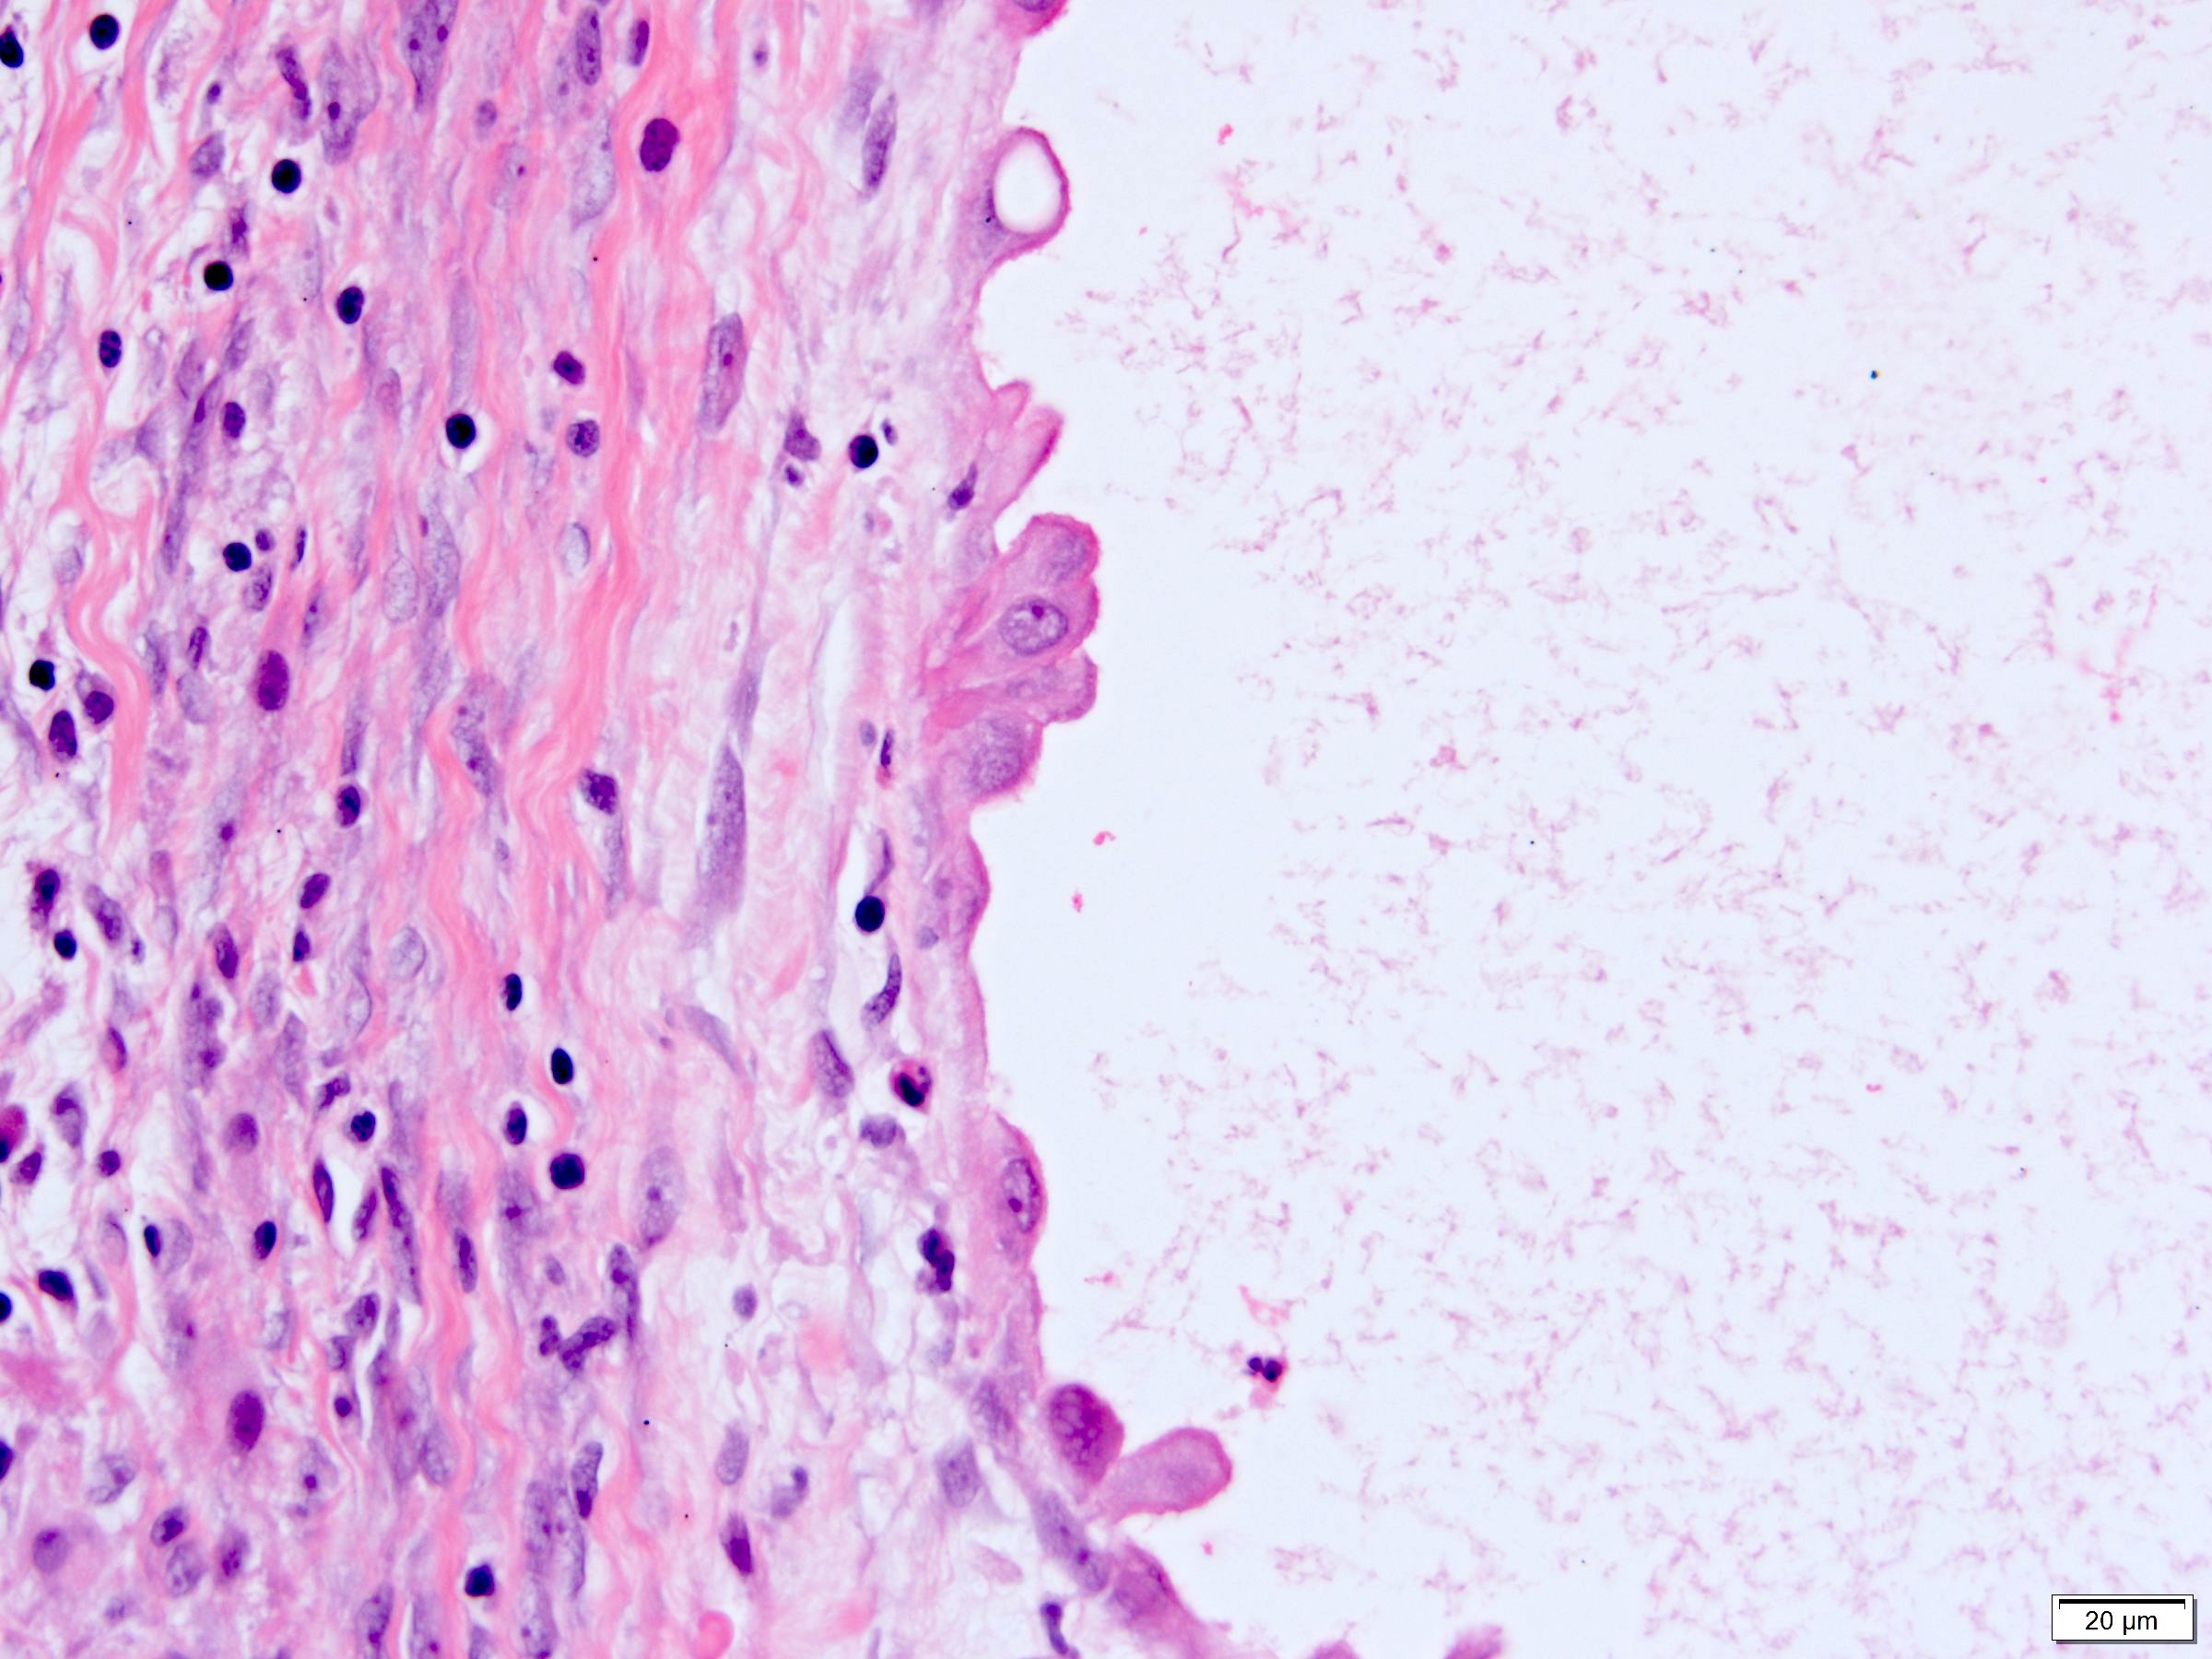

Microscopic (histologic) description

- Many with at least a partial pseudocapsule

- Entirely composed of cysts separated by septa (Semin Diagn Pathol 1998;15:2, Arch Pathol Lab Med 2004;128:1404, Am J Surg Pathol 2007;31:489, Eur Urol 2008;54:1237, Am J Surg Pathol 2016;40:1591)

- Stroma:

- Hypocellular to hypercellular

- Collagenous and fibrous to edematous and myxoid

- Areas of hyalinized stroma with contours resembling ovarian corpora albicantia

- Spindle cells; closely packed areas resemble ovarian stroma

- Cellular foci embedded with epithelial elements ranging from handful of cells with no lumen to tiny cysts with pinpoint lumens and to slightly larger cysts

- Steroidogenic cells: small clusters of polygonal cells with amphophilic cytoplasm and round nuclei, frequently around epithelial component

- Calcifications, multinucleated giant cells, foamy or hemosiderin laden macrophages and focal chronic inflammation

- Epithelium:

- Cells lining cysts

- Mostly arranged in single layer with various morphology: flat, cuboidal, hobnail, clear cell

- Rarely, foci of blunt and delicate papillae or foci of multiple layers of epithelium

- Minimal cytologic atypia

- Rare necrosis, no mitosis

Microscopic (histologic) images

A 6 cm predominantly well circumscribed, multicystic mass was incidentally found in a 55 year old woman. Sections of the partial nephrectomy showed the above histologic features. The stromal component is positive for ER and PR (shown above). What is the likely diagnosis?